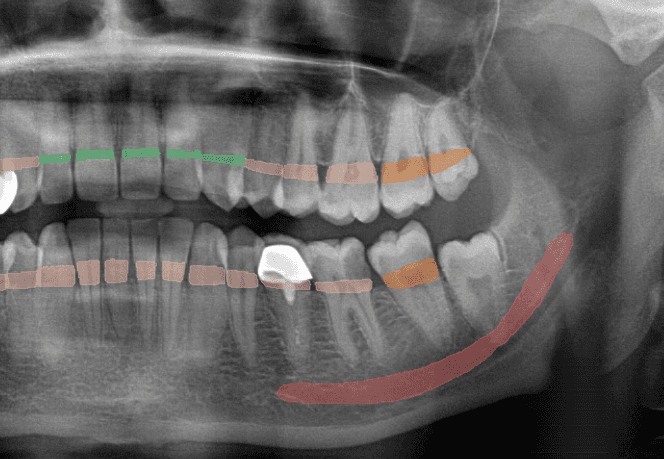

01Anatomy DetectionMay mark IAN canal, mental foramen, maxillary sinus boundaries, and root apices for clinician review

02Bone SegmentationMay support clinician review of bone levels and possible horizontal or vertical defect patterns

03Sinus DetectionMay highlight sinus boundaries and possible patterns for clinician review in planning context

04Teeth Detection & FDIMay number visible teeth using FDI notation (11-48) and associate candidate observations with positions

Periapical (PA)Candidate periapical, root, caries-depth, and endodontic observations at tooth level

Bone LossCalculusFurcation InvolvementWidened PDL SpaceVertical Bone DefectHorizontal Bone Loss